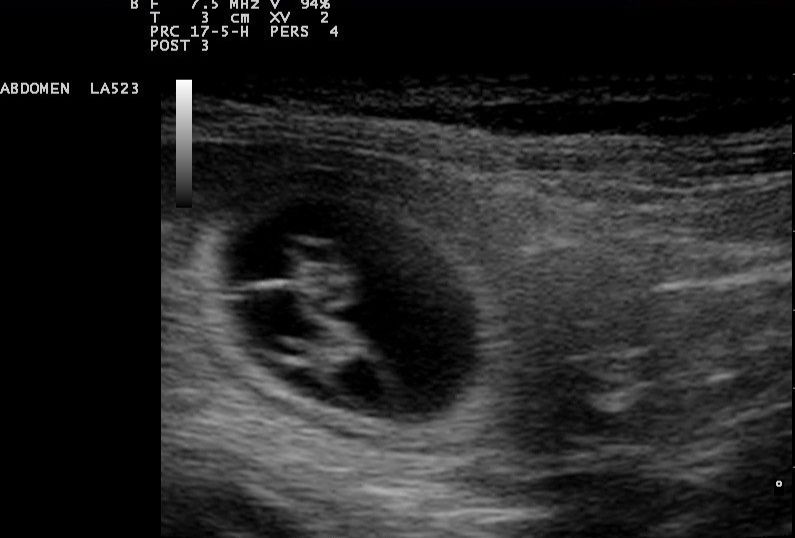

Video Otoskopie

Zur Untersuchung der äußeren Gehörgänge leistet das Video-Otoskop wertvolle Dienste.

Es ermöglicht uns den Blick ins Ohr über einen Bildschirm mit Ihnen zu teilen, um Ihnen Befunde genauer zu erläutern, sowie Bilder anzufertigen und zu speichern.